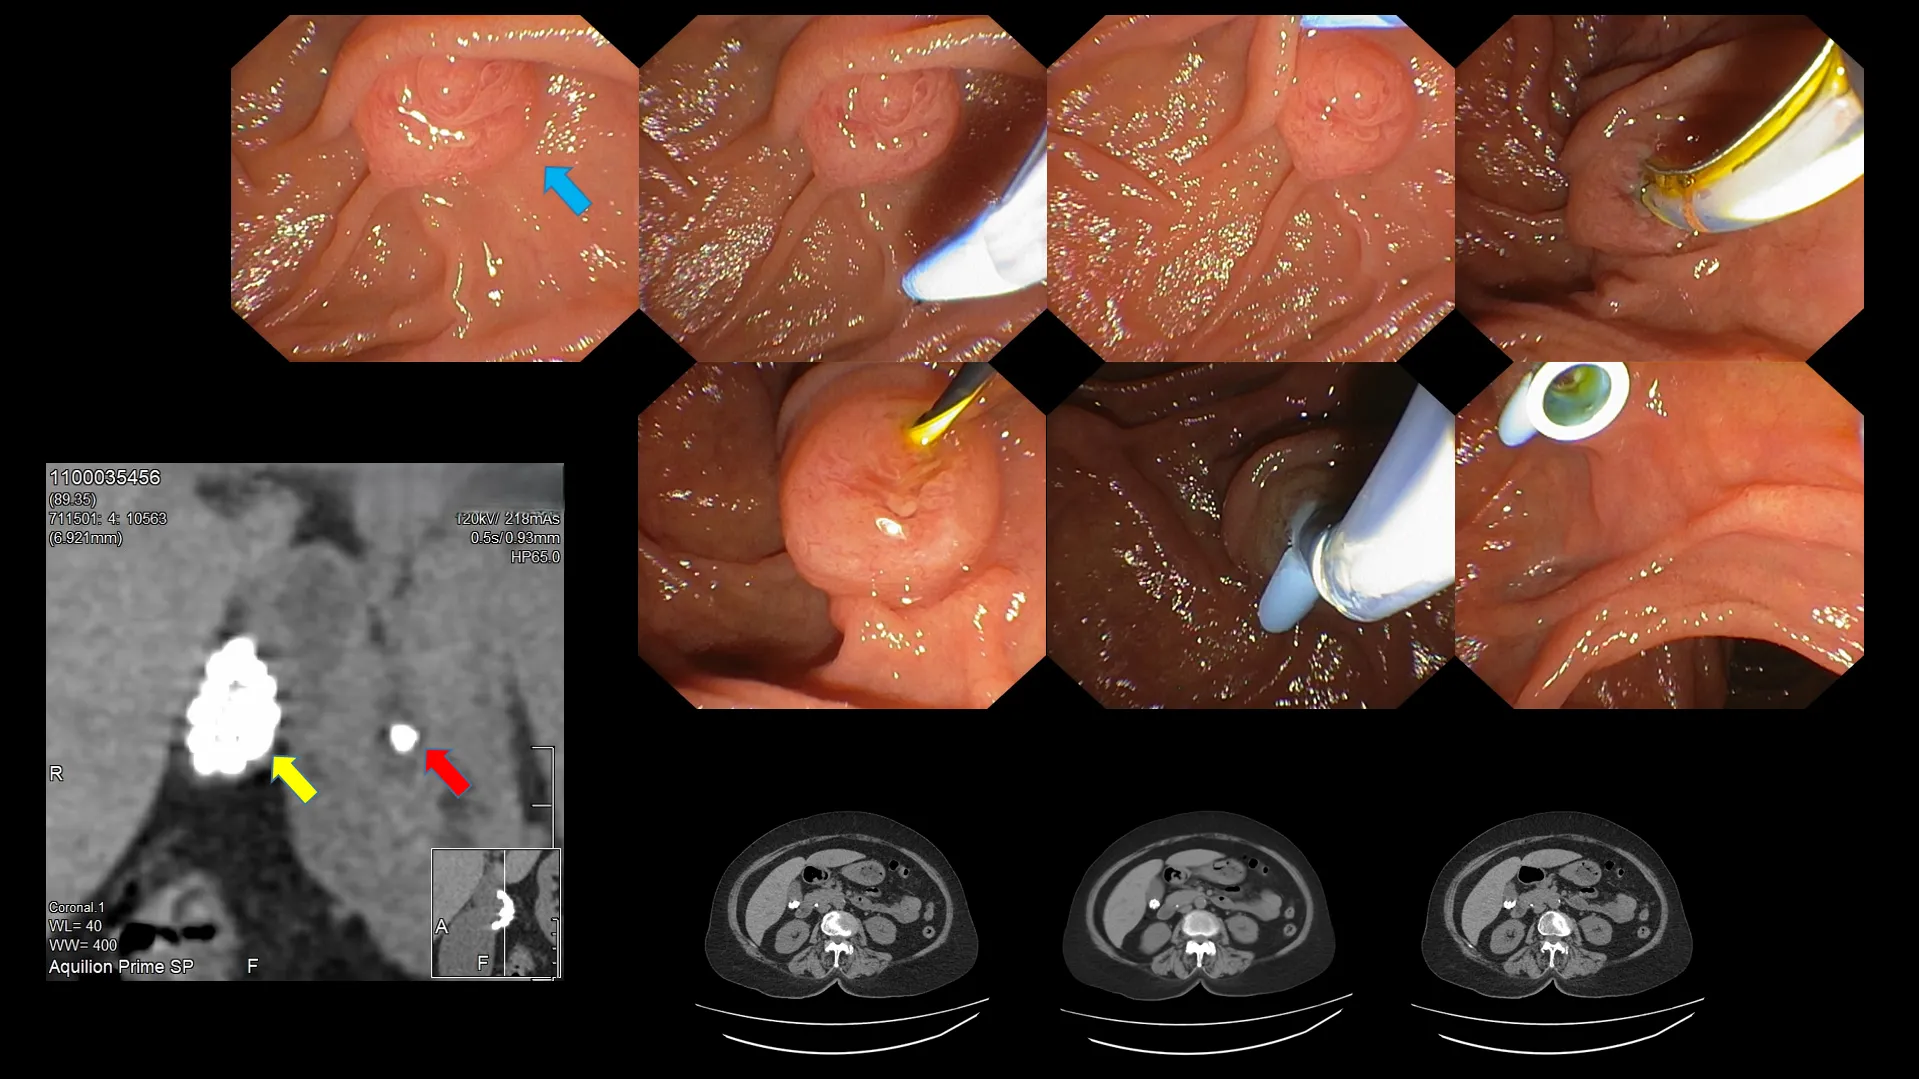

Figure 9: Choledocholithiasis (gallbladder stone within the common bile duct – yellow arrow).

Figure 10: Endoscopic retrograde cholangiopancreatography (ERCP) performed on a patient with an impacted gallbladder stone within the common bile duct (choledocholithiasis). A step-by-step approach is used to identify the doorway into the common bile duct, followed by the insertion of a catheter loaded with a guidewire into the biliary pathway. The doorway (ampulla) is then slightly cut to permit stone retrieval. Following the success of stone extraction, a temporary stent (blue tube, seen in the last row of the image above) is placed to decompress the biliary tree, allowing for the free passage of bile flow.

Figure 11: Another example with enclosed CT scan images. Gallbladder stones (yellow arrow) and an impacted stone within the common bile duct (red arrow) are visible on the CT scan. Endoscopic image of the ampulla (blue arrow). Step-by-step identification of the ampullary orifice, cannulation with a guidewire, and stent placement to facilitate bile passage.